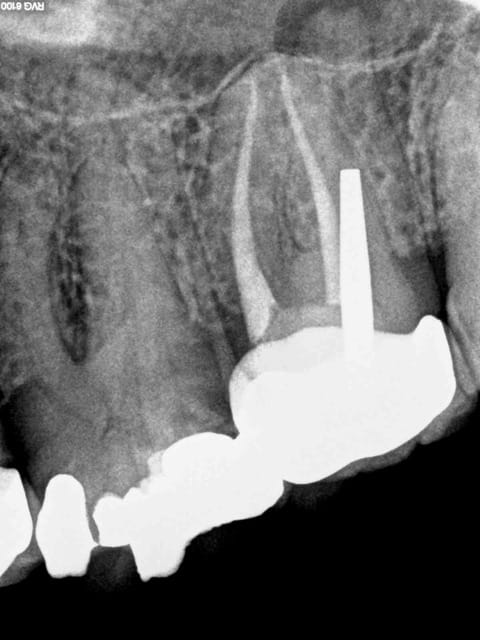

Voici toutes les radios du début à la fin :

On touche au but après 2H 30 de dépose-retraitement. Mv2 en Y heureusement pour moi. Obturation gutta chaude le tout pour 2 balles.

Le mystère reste entier concernant le canal palatin, la gutta ayant disparue probablement lors de la réalisation du tenon.

Le réchauffement de la pèche palatine a eu lieu 8 ans après.